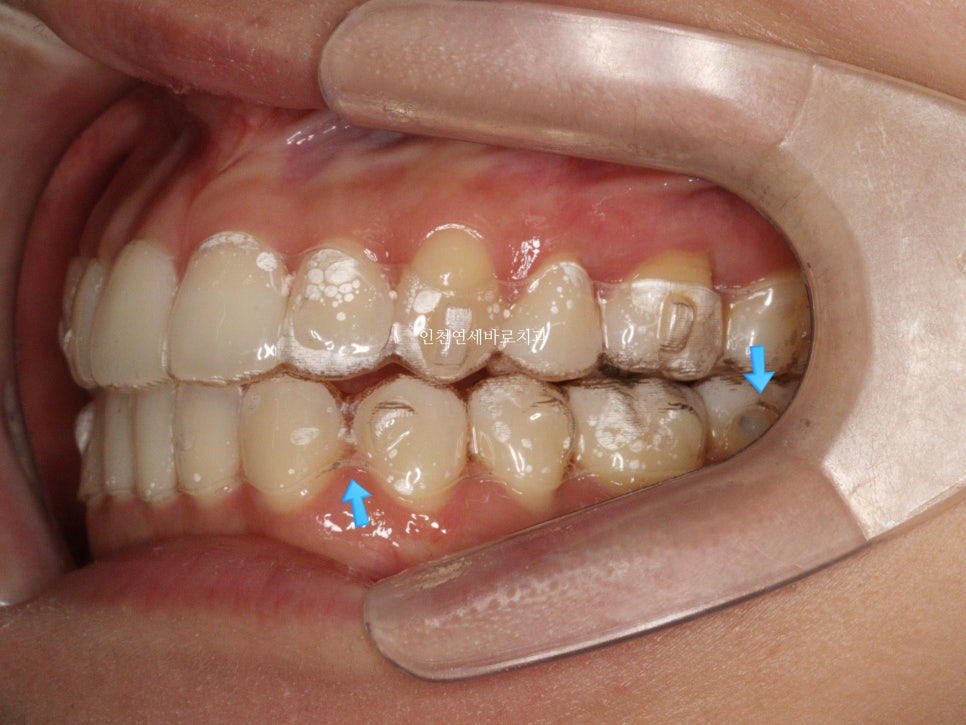

양쪽에 미니스크류 2개도 심고 중심선을 맞추기 위한 치료를 계속해나갔습니다…

그러던 중 GG

좁혀지지 않는 치아의 중심선때문에 클리피씨로 교체를 원했습니다.

이유는 다양합니다.

분명 장치도 문제되지 않을 정도로 꽤 잘맞고, 치료계획도 좋았지만 지친 환자분을 설득하기엔 이미 퇴사하신 분.